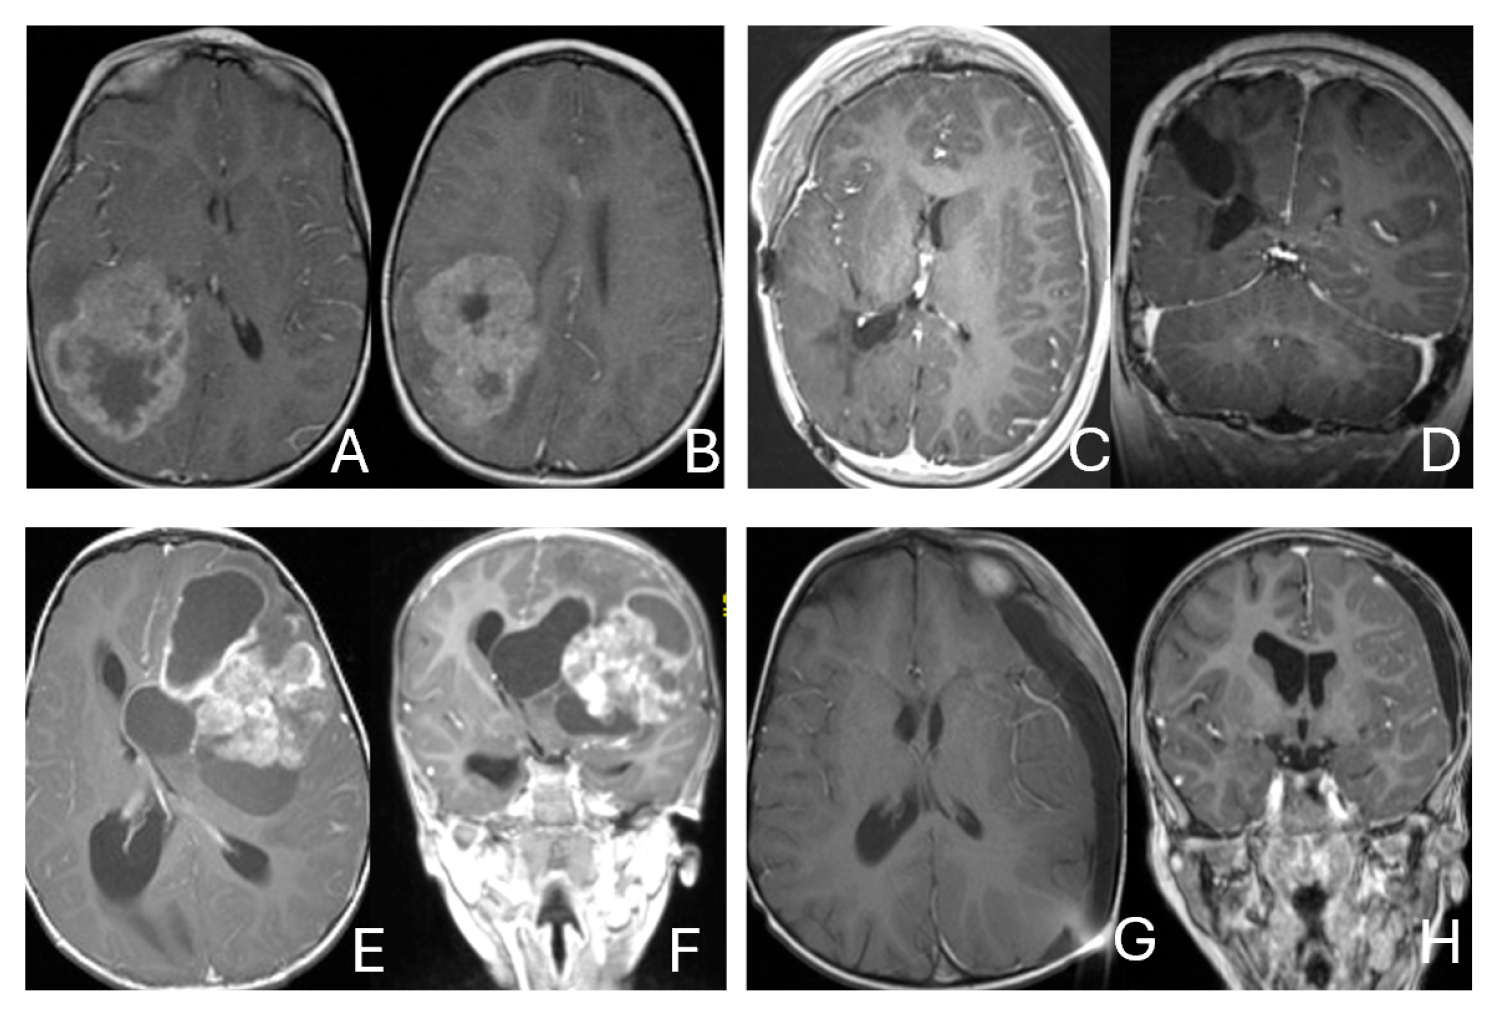

Tumor epicenters and patterns of extension were best delineated by operative observations combined with preoperative and postoperative imaging (Figure 1). Three patients had tumors involving both the temporal and frontal lobes that crossed the Sylvian fissure (Figure 2). Despite appearance of thalamic involvement on preoperative imaging, two patients had tumors primarily occurred in the basal ganglia, which became more evident on postoperative MRI (Figure 3). Additional hemispheric tumor extended into the thalamus. These lesions were resected via a trans-sylvian approach.

Figure 1.

Cerebral lobar ATRT. (A–D): 20-month-old boy with a parietal intraparenchymal ATRT. Preoperative axial images (A,B) and postoperative axial (C) and coronal (D) images confirm the intraparenchymal location following resection. (E–H): 26-month-old boy with a large heterogeneous frontal mass with multiple peritumoral cysts. Preoperative axial (E) and coronal (F) images, and postoperative axial (G) and coronal (H) images after gross-total resection support a frontal lobe origin despite of the basal ganglia origine as the preoperative imaging suggetsed.

Figure 3.

Basal ganglia ATRT. (A–D): Post contrast MR images ((A)-axial, (B)-coronal) of 13-month-old boy with deep seated ATRT. Note the solid tumor with peritumoral cysts at the basal ganglia with one cyst extending to the thalamus. Post-resection MR images ((C)-axial, ((D)-coronal) show the tumor resected cavity in the basal ganglia with the thalamus clear of tumor involvement. (E–H): Post contrast MR images ((E)-axial, (F)-coronal) of a 23-month-old boy with a large ATRT of deep temporal lobe and the insula extending to the basal ganglia. The tumor was predominantly in the basal ganglia as shown postoperative MR ((G)-axial, (H)-coronal).